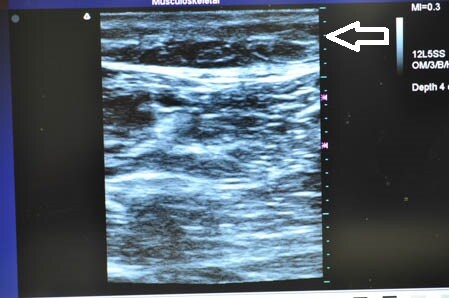

最後に参考までに今回の患者様の

硬膜外麻酔(患者様はこれをたくさんインスタでご覧になったそうです)と

術中の模様を紹介しましょう。